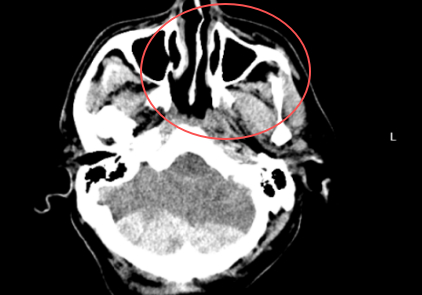

PART01危重患者緊急入院4月18日凌晨3時,一名因醉酒摔倒致頭部外傷、意識模糊的患者被緊急送至我院急診科。入院時患者頭部持續(xù)出血、右側(cè)肢體偏癱,頭顱CT檢查提示“左側(cè)額葉腦挫裂傷合并左側(cè)額顳部硬膜下血腫”,病情危重。凌晨3點急診CT神經(jīng)外科團隊迅速響應(yīng),嚴(yán)密監(jiān)測患者生命體征。然而,隨著時間推移,患者頭痛加劇,復(fù)查CT顯示顱內(nèi)血腫范圍擴大,腦組織受壓明顯,需立即手術(shù)干預(yù)。上午9點CT復(fù)查PART02血腫擴大危及生命面對緊急情況,神經(jīng)外科趙堅柱副主任醫(yī)師帶領(lǐng)團隊快速制定手術(shù)方2025-04-26